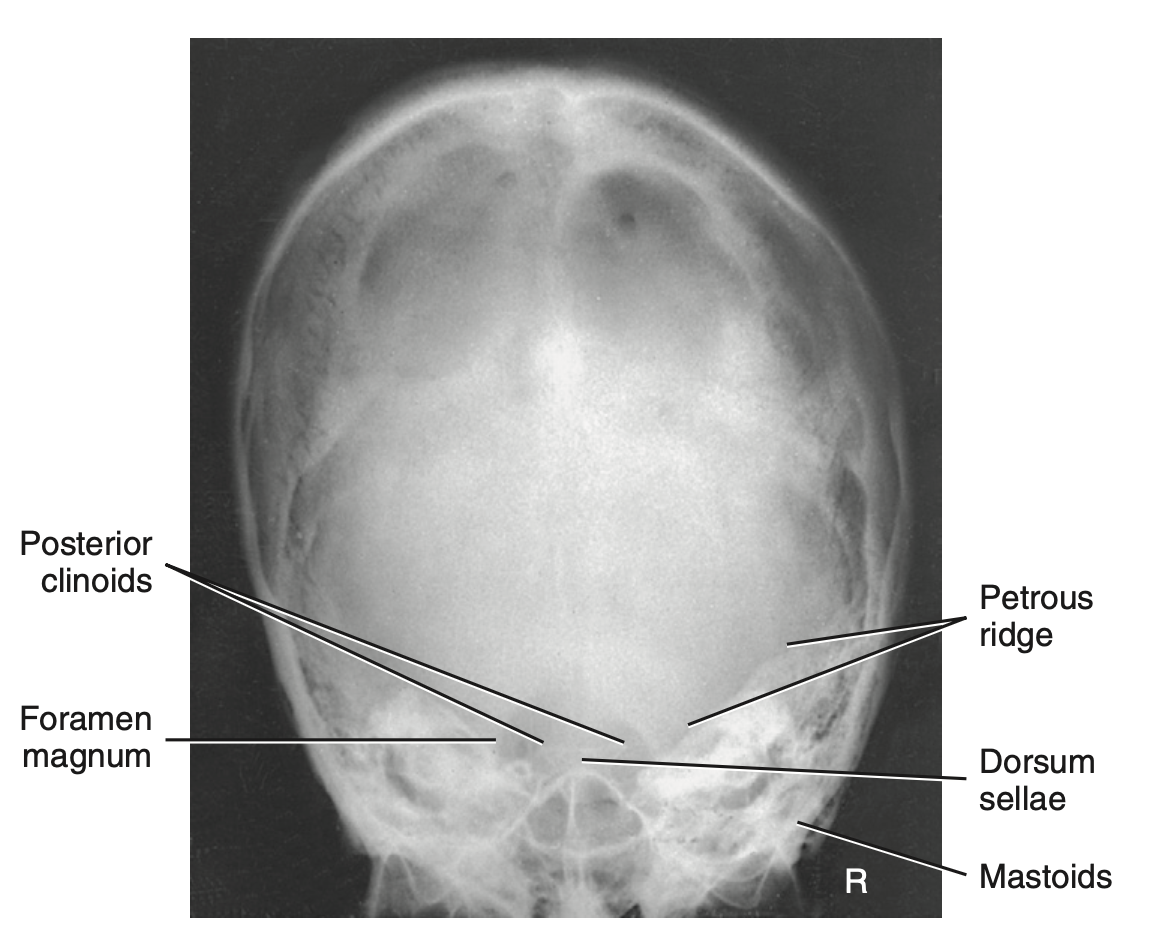

Skull critique:

Dorsum sellae and posterior clinoid processes in the shadow of the foramen magnum

Petrous ridges are symmetrical

How do you critique radiograph of AP axial projection of Towne’s method for skull?